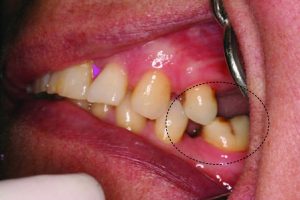

Depending on the severity of the problem, either the denture base is altered or the tuber’s lowering is surgically adjusted to make room for the prosthesis. The molar may tip mesially as a result of posterior tooth loss (Figure 10-17).

Figure 10-17. Loss of teeth in the posterior region may cause the lower molar to drift mesially and the upper premolars to drift distally.